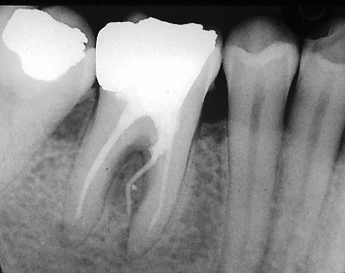

Lorsque la perforation est ancienne et a été à l’origine d’une lésion interradiculaire, il faudra faire une hémisection et un curetage inter radiculaire en taillant 2 monoradiculées à la place d’une biradiculée.

La dent est transformée en deux dents avec possibilité de passer des brossettes interdentaires.

On obtient un septum et une papille interdentaire en bonne santé.